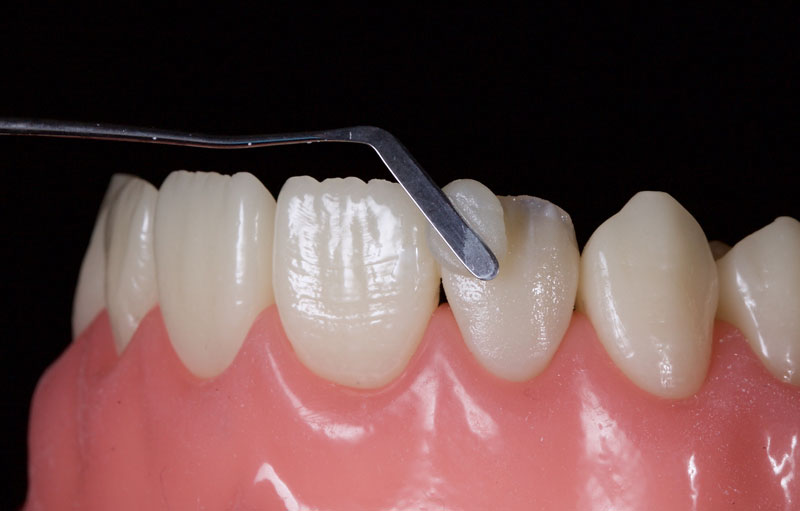

- Minimal tooth preparation/reduction (Fig. 6): This is employed when orthodontics is declined or if the patient already has a Class I incisal relationship with an acceptable overjet and overbite.

This is best achieved by cutting uniform 1.0 mm-deep cuts (dimples or grooves). The tooth is then reduced with a coarse crown diamond, followed by polishing with fine diamonds/discs to smooth the enamel and reduce the risks of white lines due to “enamel peel” (cohesive enamel failure). Typically, only the incisal-facial half must be reduced, leaving the gingiva untouched.